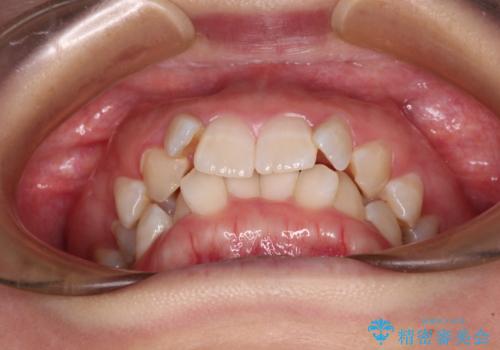

- 上下前歯のデコボコを気にして来院された患者様です。

口元の突出感はあまりなかったものの、デコボコを非抜歯で改善すると出っ歯になる可能性があるため、上下左右の第一小臼歯4本を抜歯し、ワイヤー装置にて矯正治療を行うこととしました。